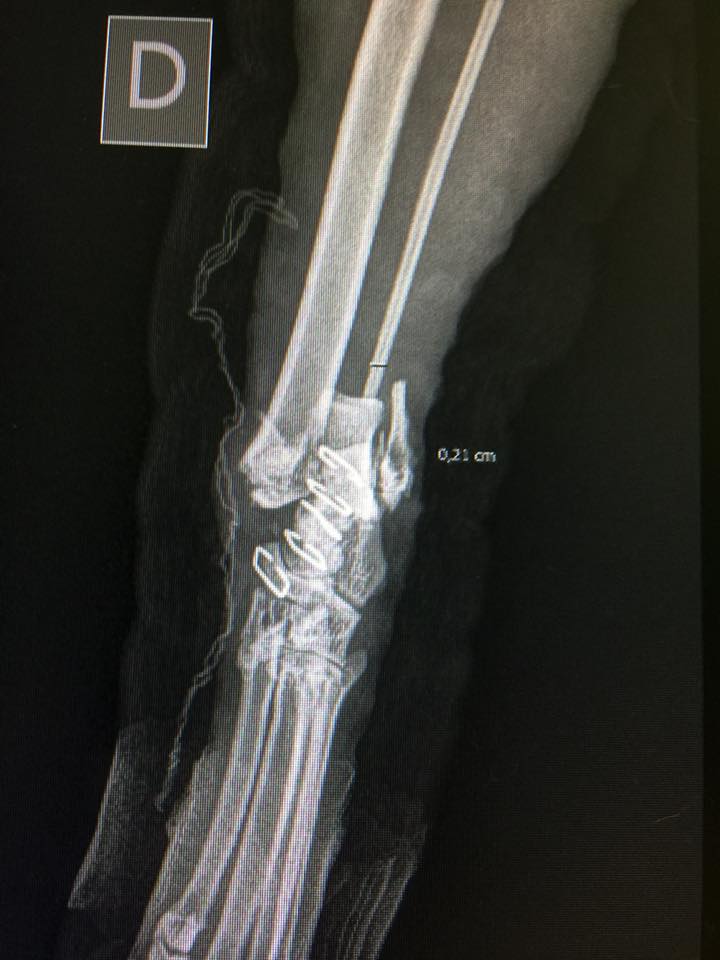

Ogni tanto, infatti, capitano in Clinica gatti che hanno sperimentato questa brutta esperienza. Le lastre che vedete in questo post sono tutte relative a un solo gatto, che caduto dal settimo piano si è fratturato almeno un osso per ogni arto. Che fare se accade qualcosa del genere? Il gatto va ovviamente portato immediatamente dal veterinario, ma cercando di toccarlo/spostarlo il meno possibile, perché sente dolore e perché potreste peggiorare i danni.